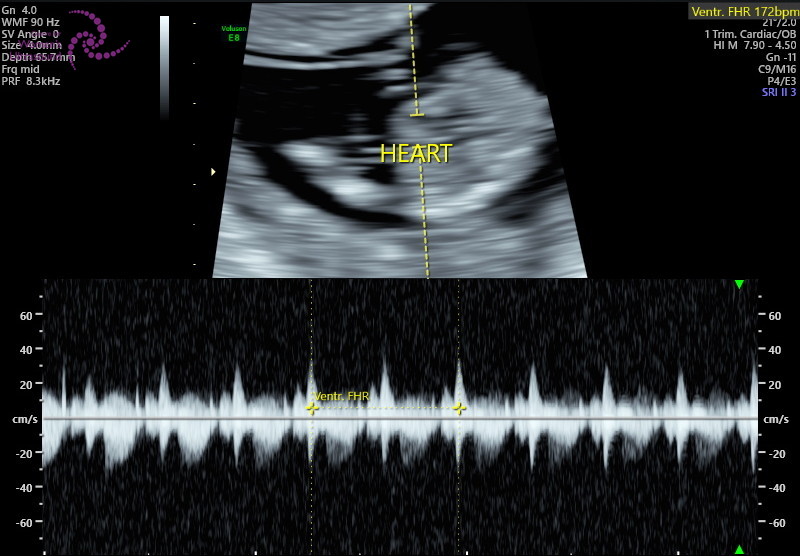

저희는 7주 초음파 때

심장소리를 안 들려줘서

이번에 처음 듣는 건데

드라마에서 보는 것처럼 눈물이 막 나고

그러진 않더라고요